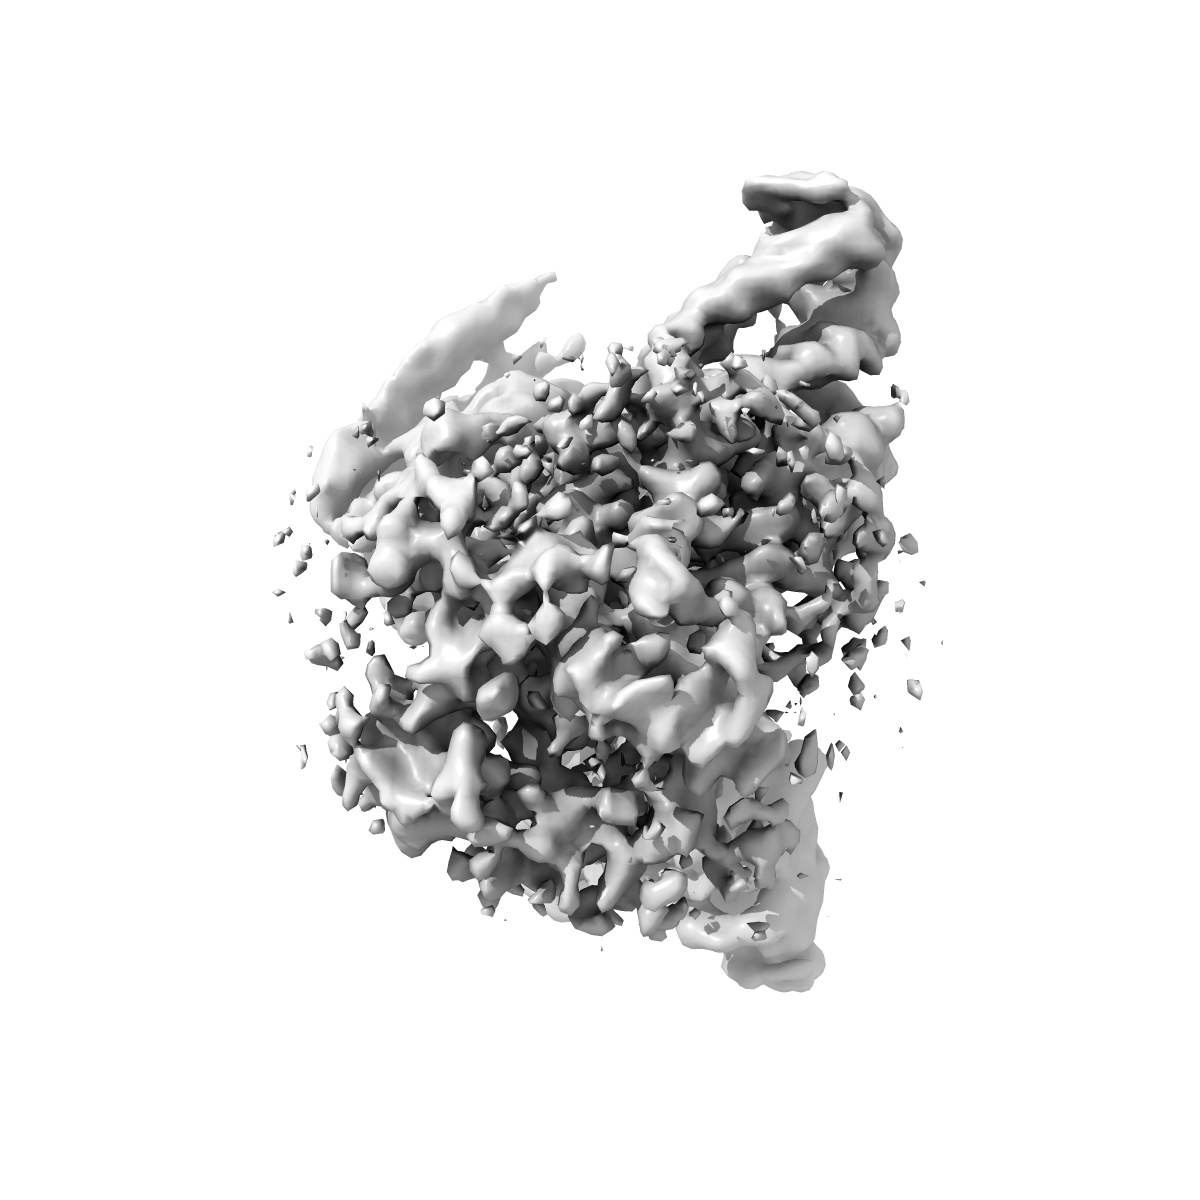

Structure of CXCR3 in the apo-state (Receptor focused map)

Single-particle3.68 Å

Sample: C-X-C chemokine receptor type 3 in complex with Go

Fitted models: 8xxy

Structural visualization of small molecule recognition by CXCR3 uncovers dual-agonism in the CXCR3-CXCR7 system.

(2025) Nat Commun , 16 , 3047 - 3047